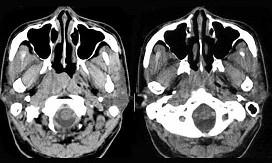

男,52岁,右耳鸣两月余,伴鼻塞,CT如图所示,应诊断为()A.鼻咽淋巴瘤B.鼻咽纤维血管瘤C.增殖体肥大D.鼻咽癌E.鼻咽部慢性炎症

问题 男,52岁,右耳鸣两月余,伴鼻塞,CT如图所示,应诊断为()

选项 A.鼻咽淋巴瘤 B.鼻咽纤维血管瘤 C.增殖体肥大 D.鼻咽癌 E.鼻咽部慢性炎症

答案 D